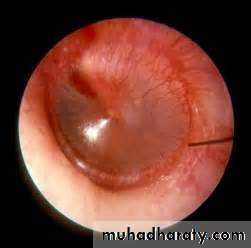

exam _ red t.m.

_ bulging.

PerforationOedematous mucosa of the tympanic Cavity

Occasionally aural polyp or granulation tissue

• Discharge ; often scanty mucoid, but becomes copious & purulent during exacerbation of U.R.T.I.• Conductive deafness

• Perforation // attic or mariginal

• Cholesteotoma may be visible as keratin leaf